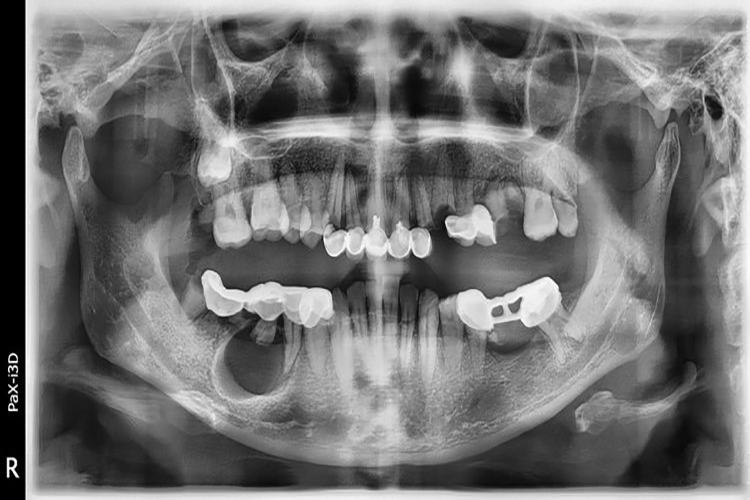

早期牙源性颌骨囊肿诊断较难,依据病程长短,肿物部位,触诊时发生乒乓球感或波动感,X线检查,穿刺及穿刺液涂片显微镜下检查也有助于诊断。非牙源性颌骨囊肿根据囊肿发生部位及牙髓是否存在活力等特征诊断。

囊肿生长缓慢,初期无自觉症状,为慢性无痛性生长。骨质逐渐向周围膨胀形成颌骨膨隆,严重时造成面部畸形。

囊肿如继发感染,可有局部红肿、触压痛甚至脓肿形成,并可伴有发热等。巨大的颌骨囊肿可致牙松动、移位、脱落及咬合紊乱,影响进食。